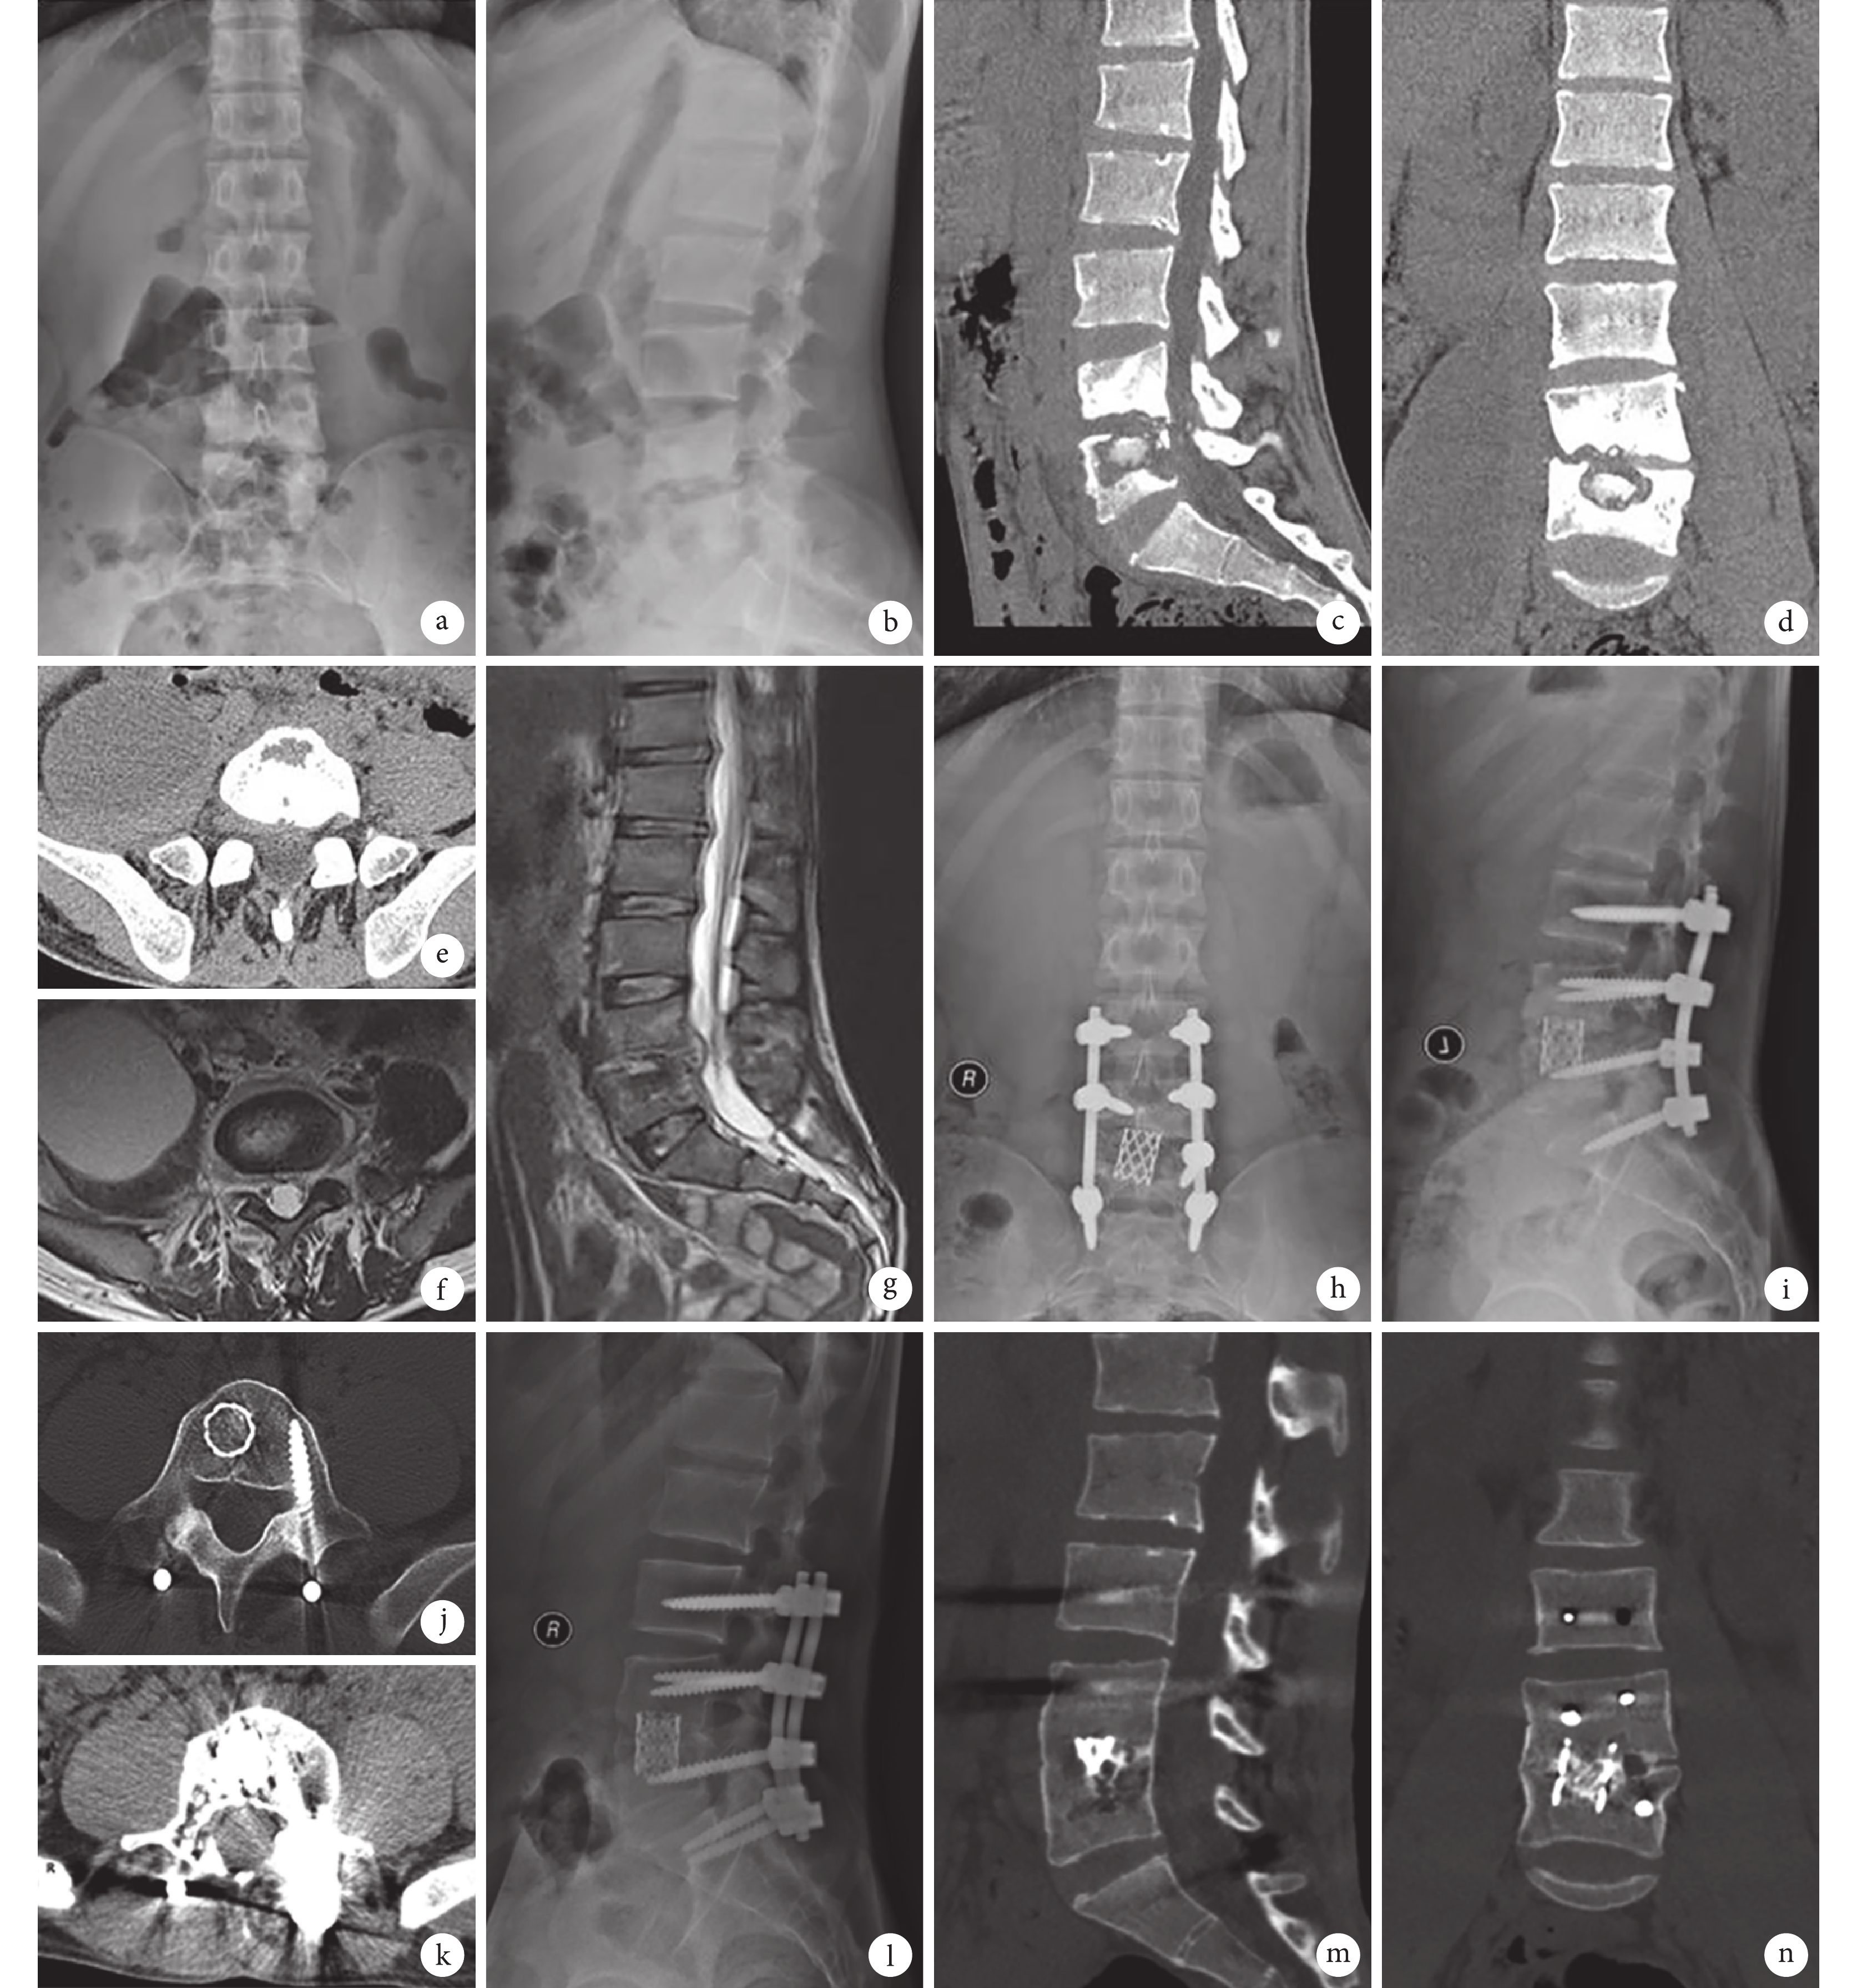

a、b. 術前腰椎正側位 X 線片;c~e. 術前 CT;f、g. 術前 MRI;h、i. 術后 7 d 正側位 X 線片示,內固定物位置良好;j、k. 術后 4 個月橫斷面 CT 示,右側腰大肌膿腫消失,雙側腰大肌形態基本一致;l~n. 術后 7 個月腰椎側位 X 線片及三維 CT 示,病灶愈合及植骨融合滿意,腰椎生理曲度良好

Figure1. A 22-year-old male patient with spine tuberculosis (L4, 5) with right psoas abscessa, b. Anteroposterior and lateral X-ray films before operation; c-e. CT scan before operation; f, g. MRI before operation; h, i. Anteroposterior and lateral X-ray films at 7 days after operation, showing good location of internal fixation; j, k. Cross-section CT at 4 months after operation, showing right psoas abscess disappeared, bilateral psoas basically the same shape; l-n. Lateral X-ray film and three dimensional CT at 7 months after operation, showing the lesion healed well and the fusion was satisfactory, lumbar physiological curve was good

A 組 1 例 L4、5 結核患者術后 29 個月隨訪時內固定物斷裂,節段矯形部分丟失,局部已骨性融合,患者無特殊不適,予以取出內固定物。B 組 1 例 L4、5 結核、腎衰尿毒癥期患者,經前路膿腫清除,隨訪期間因腎性骨病、骨質疏松等逐漸出現節段矯形部分丟失,但無明顯腰痛不適;患者因腎衰伴腎性高血壓、高尿酸血癥等,予以個體化抗結核治療及抗骨質疏松治療。見圖 1、2。兩組患者末次隨訪時病變節段 Cobb 角較術前顯著改善,差異有統計學意義(P<0.05);末次隨訪時兩組間比較病變節段 Cobb 角以及矯正度,差異無統計學意義(P>0.05)。見表 2。術前 9 例伴脊髓神經損傷者中,2 例 ASIA C 級恢復至 D 級 1 例、E 級 1 例,7 例 ASIA D 級均恢復至 E 級,與術前比較差異有統計學意義(Z=–2.716,P=0.007)。A 組 4 例、B 組 5 例隨訪期間出現藥物性肝腎功能損害,主要表現為高尿酸血癥、轉氨酶升高及膽紅素升高等,予以調整抗結核藥及保肝等治療后好轉。